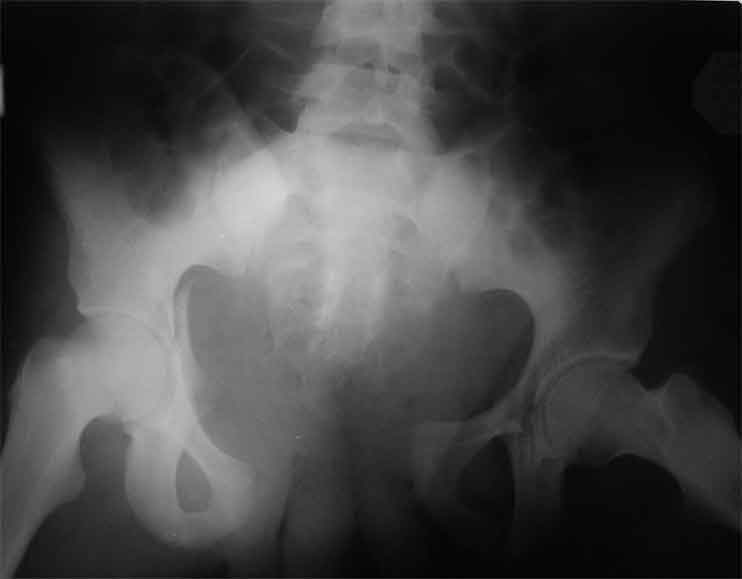

продолжение темы. не увидел энтузиазма в обсуждении. Вопросы прежние, первым этапом закрыто устранили вертикальное и передне-заднее смещение. Каким образом восстановить целостность тазового кольца, из каких доступов? Снимки в приложении

передне-неружным внебрюшинным доступом к лонно-седалищномц сочленению - синтез штангами(можно из заднего доступа, но хуже обзор и труднее репозиция), из этого же доступа к крыше вертлужной впадины - синтез реконструктивными пластинами(мы делали "ChM" тазовыми, хорошо себя зарекомендовали), передним доступом на лонное сочленение - синтез подобной пластиной. к задней колонне вертлужной впадины - задне-наружный доступ, синтез такой же пластиной. КРОВОПОТЕРЯ!!! возможно до 7л. мощная ангтибак. профилактика во время и после операции. до перехода на заднюю колонну оперировать в аппарате. бвл подобный случай, по снятии аппарата через 8 мес. - рецедив смещений сразу.